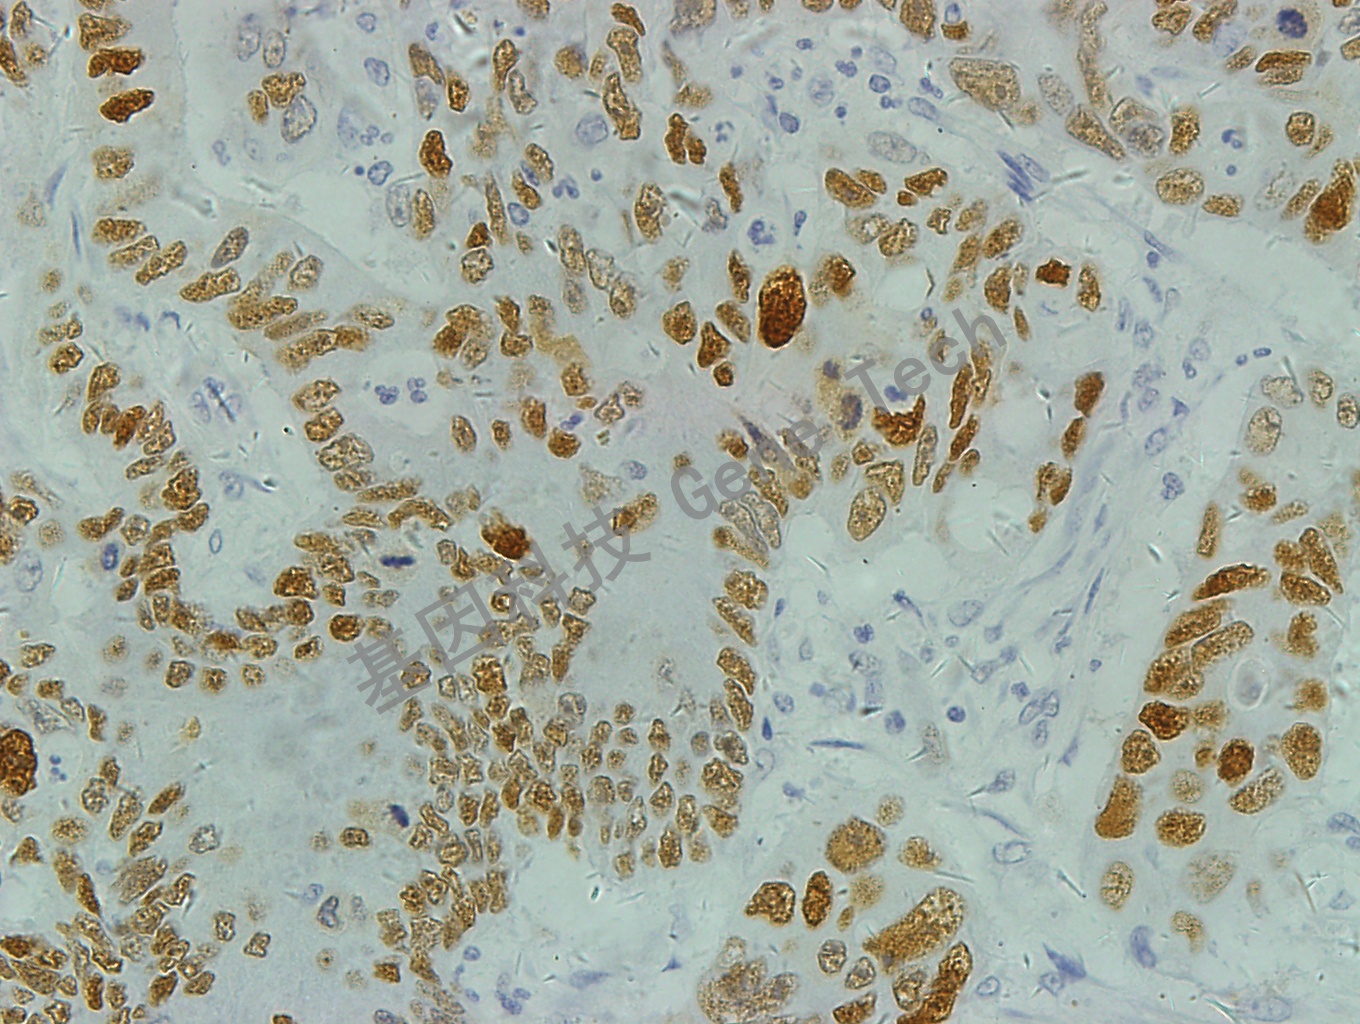

结肠癌石蜡切片,用 p53(GT2095)染色,细胞核着色,DAB 显色。